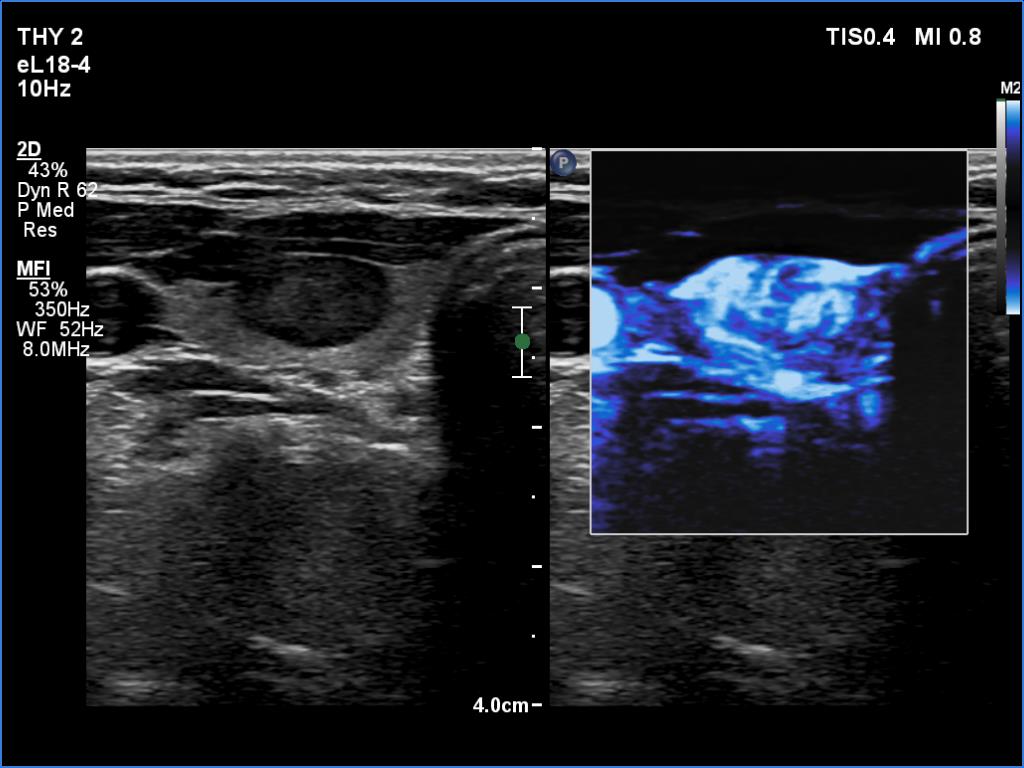

Ultrasonography. The thyroid was echonormal. There was a moderately hypoechoic nodule in the ventral part of the right lobe. This lesion has regular, sharp margins and presented signs of a possible extrathyroidal spread. The intranodular vascularity was increased. The left lobe had a tiny, minimally hypoechoic lesion. The largest diameter was 7 mm. The lesion had both echogenic lines and granules, a pattern corresponding either to connective tissue or back wall figure. The lesion had neither halo nor perinodular blood flow.

The original sin was the misinterpretation of connective tissue as microcalcification.

The third was the handling of the cytology. This was not the failure of the colleagues but the failure of our current practice. If we follow the suggestions, we cannot take clinical or ultrasound data into account when giving a cytological diagnosis. It is very strange because in the histopathological diagnosis, these data are taken into account. Moreover, while in histopathology, the consideration of these data only rarely influences the final diagnosis, in cytology, this consideration would have a huge impact. Regarding this case, a nodule which does not show any ultrasound signs of a capsule, is unlikely a follicular tumor; this lesion did not have either a halo sign or perinodular blood flow.